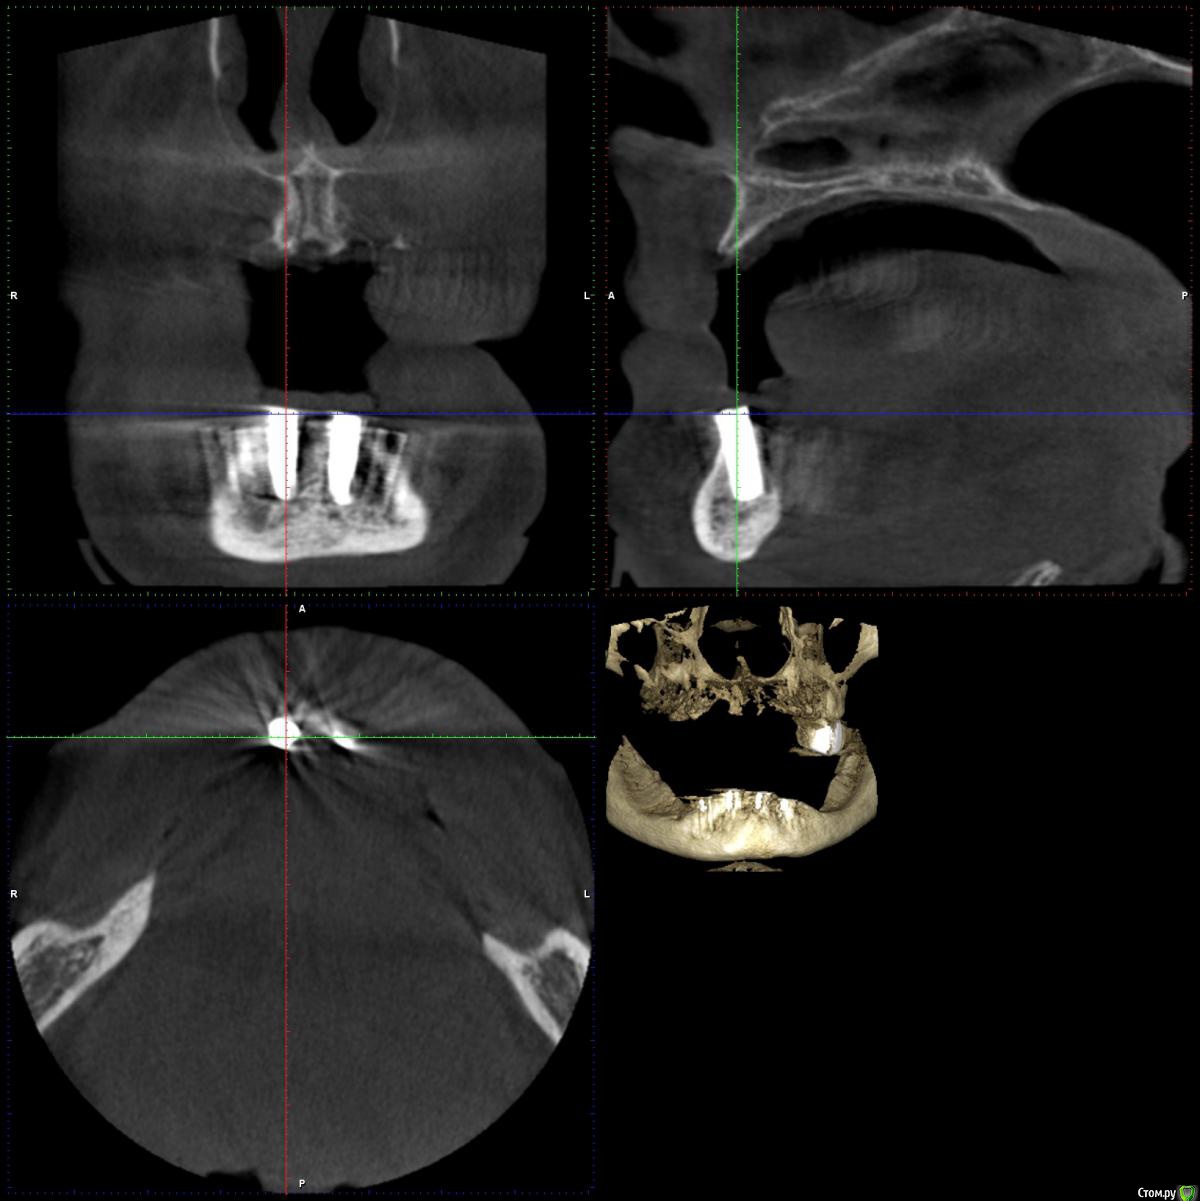

Артур К. Опубликовано 5 июня, 2016 Поделиться Опубликовано 5 июня, 2016 Добрый день! Пациенту (женщина, 50 лет) три месяца назад установили 4 импланта (BEGO Semados, если это имеет значение) в нижнюю челюсть под установку протеза. Один из имплантов (второй справа) до сегодняшнего дня причиняет дискомфорт, а при давлении сверху (просто небольшое давление пальцем на десну) боль. Не острая, но вынуждает всё это время исключать правую часть челюсти из жевания (на нижней челюсти съемный протез). В течение примерно месяца после операции в районе этого импланта был небольшой, но заметный отёк. При этом никаких признаков воспаления нет, врач говорит, что всё нормально и на ближайшее время назначает установку формирователей десны. На вопрос о причине боли разводит руками. Подскажите, пожалуйста, насколько это нормально, в чём может быть причина боли? Есть ли смысл не торопиться с установкой формирователей десны и обратиться к другому специалисту за консультацией? Врачу доверяем, но по всем отзывам имплант не должен причинять никакой боли (так и есть с тремя остальными), а установка протеза при сохранении боли вообще становится бессмысленной. Ссылка на комментарий